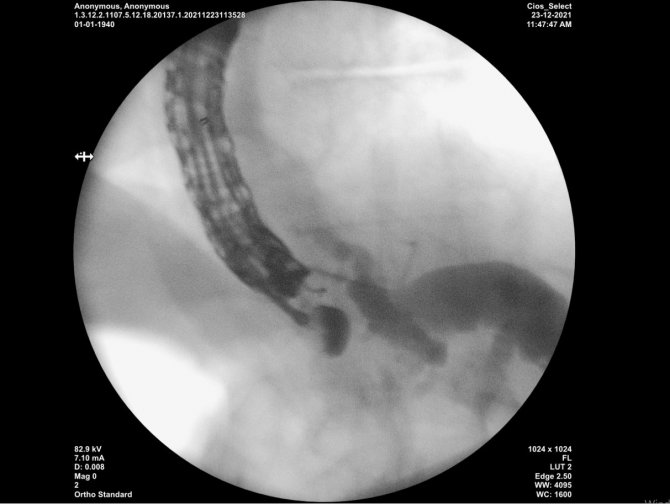

Kayseri Şehir Hastanesi'nde safra yolu tıkanıklığı şikayetiyle başvuran hastaya uygulanan endoskopik ultrason yöntemi ile bir ilk gerçekleştirildi. Kayseri Şehir Hastanesi Gastroenteroloji Kliniği Sorumlusu Doç. Dr. Serkan Doğan'ın yaptığı uygulama ile midesi delinerek karaciğere, ardından da safra yollarına ulaşılan hastanın safra yolu ameliyatsız bir şekilde boşaltıldı. Uygulama hakkında bilgiler veren Doğan, "Biz burada birçok ileri düzey işlemi yapabilmekteyiz. Tabi ki tıpta ki olan gelişmeler ile işlemin sonu belli değil. Her gün yeni teknikleri çıkıyor. Bizim yaptığımız işlem, safra yollarındaki tümörün tedavisinde kullanılan ve stent ile yapılan bir işlem. Hastalarımız cerrahi olarak tedavi edilecek durumdalarsa cerrahlarımıza veriyoruz. Ancak cerrahi olarak hasta ameliyat edilemiyorsa safranın bir şekilde akması lazım. Çünkü hastalar çok ciddi bir düzeyde sarılıkla geliyorlar. Bu tıkanıklığı açmak için normalde vücut dışında olan ve iğne ile girilen, torbaya biriken safra akımı mevcutken, biz mideyi delerek sonrasında karaciğere geçiyoruz. Ardından da safra yollarına ulaşarak, aradaki bağlantıyı stent sağladık. Bu stent yerleştirirken ki görüntülemem yöntemimiz de endoskopik ultrason cihazıylaydı. Bu gerçekleştirdiğimiz mide ile karaciğer arasındaki bağlantıyı stentle kurma işleminde hem normal endoskop hem x-ray cihazı hem de endoskopik ultrason cihazı olmak üzere 3 tane görüntüyü aynı anda bir arada çalıştırarak ekip halinde yaptığımız bir işlem" ifadelerini kullandı.

Doğan, "Safra akması dışarıya bir torba gibi olurken, şimdi yaptığımız işlemle her şey içeriden oluyor. Yani bir ucu midede bir ucu safra yolunda bir stent şekilde oluyor. Bu tür hastalar zaten maalesef çok uzun bir ömür beklemediğimiz, ameliyat şansı olmayan hastalar. Biz istiyoruz ki hastaların sarılığı olmasın. Bunu da bu işlem ile başarmış oluyoruz. Bundan sonra da yapmaya devam edeceğimizi düşünüyoruz. Bu işlemimizde başarılı olabilirsek, dışarıdan sürekli safranın aktığı bir torba ile dolaşmak yerine hastanın stent yoluyla midesine safranın akması hastaya oldukça büyük bir konfor sağlıyor" dedi.